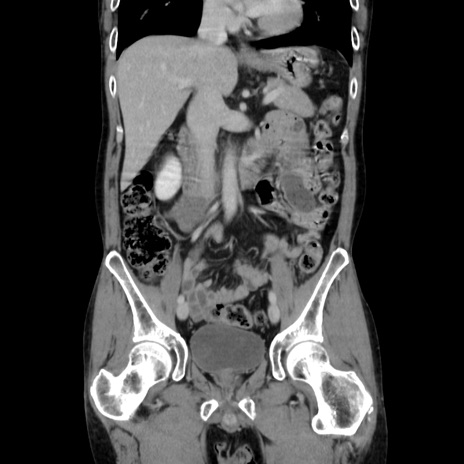

症例37(冠状断像)

【症例】40歳代 男性

【主訴】腹痛

【現病歴】4時間ほど前に電車に乗車中に臍部上より腹痛出現。徐々に増悪し起立困難となり、救急外来受診。生ものは数日食べていない。今朝お雑煮を食べた。

【身体所見】BT 36.8℃、BP 117/84mmHg、HR 91/min、SpO2 97%、苦悶様、腹部:臍上部広範囲圧痛あり、反跳痛±

【データ】WBC 8100、CRP 0.03